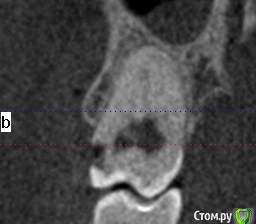

shurkne Опубликовано 7 марта, 2015 Поделиться Опубликовано 7 марта, 2015 (изменено) Скажите удалять ли 1.8 или лечить?глубокий прищечный кариес....пульпит Изменено 7 марта, 2015 пользователем shurkne Ссылка на комментарий

red_butler Опубликовано 7 марта, 2015 Поделиться Опубликовано 7 марта, 2015 а почему не лечить?если сильно хочется, то лечите, по снимку похоже на пульпит, в этом случае протезируйте коронкой. И наладить гигиену. Зуб уже лечен и появился новый кариес, что говорит о огрехах в гигиене. Я бы рекомендовал заниматься участками потерянных зубов, а восьмерку отпустить.Решать Вам Ссылка на комментарий